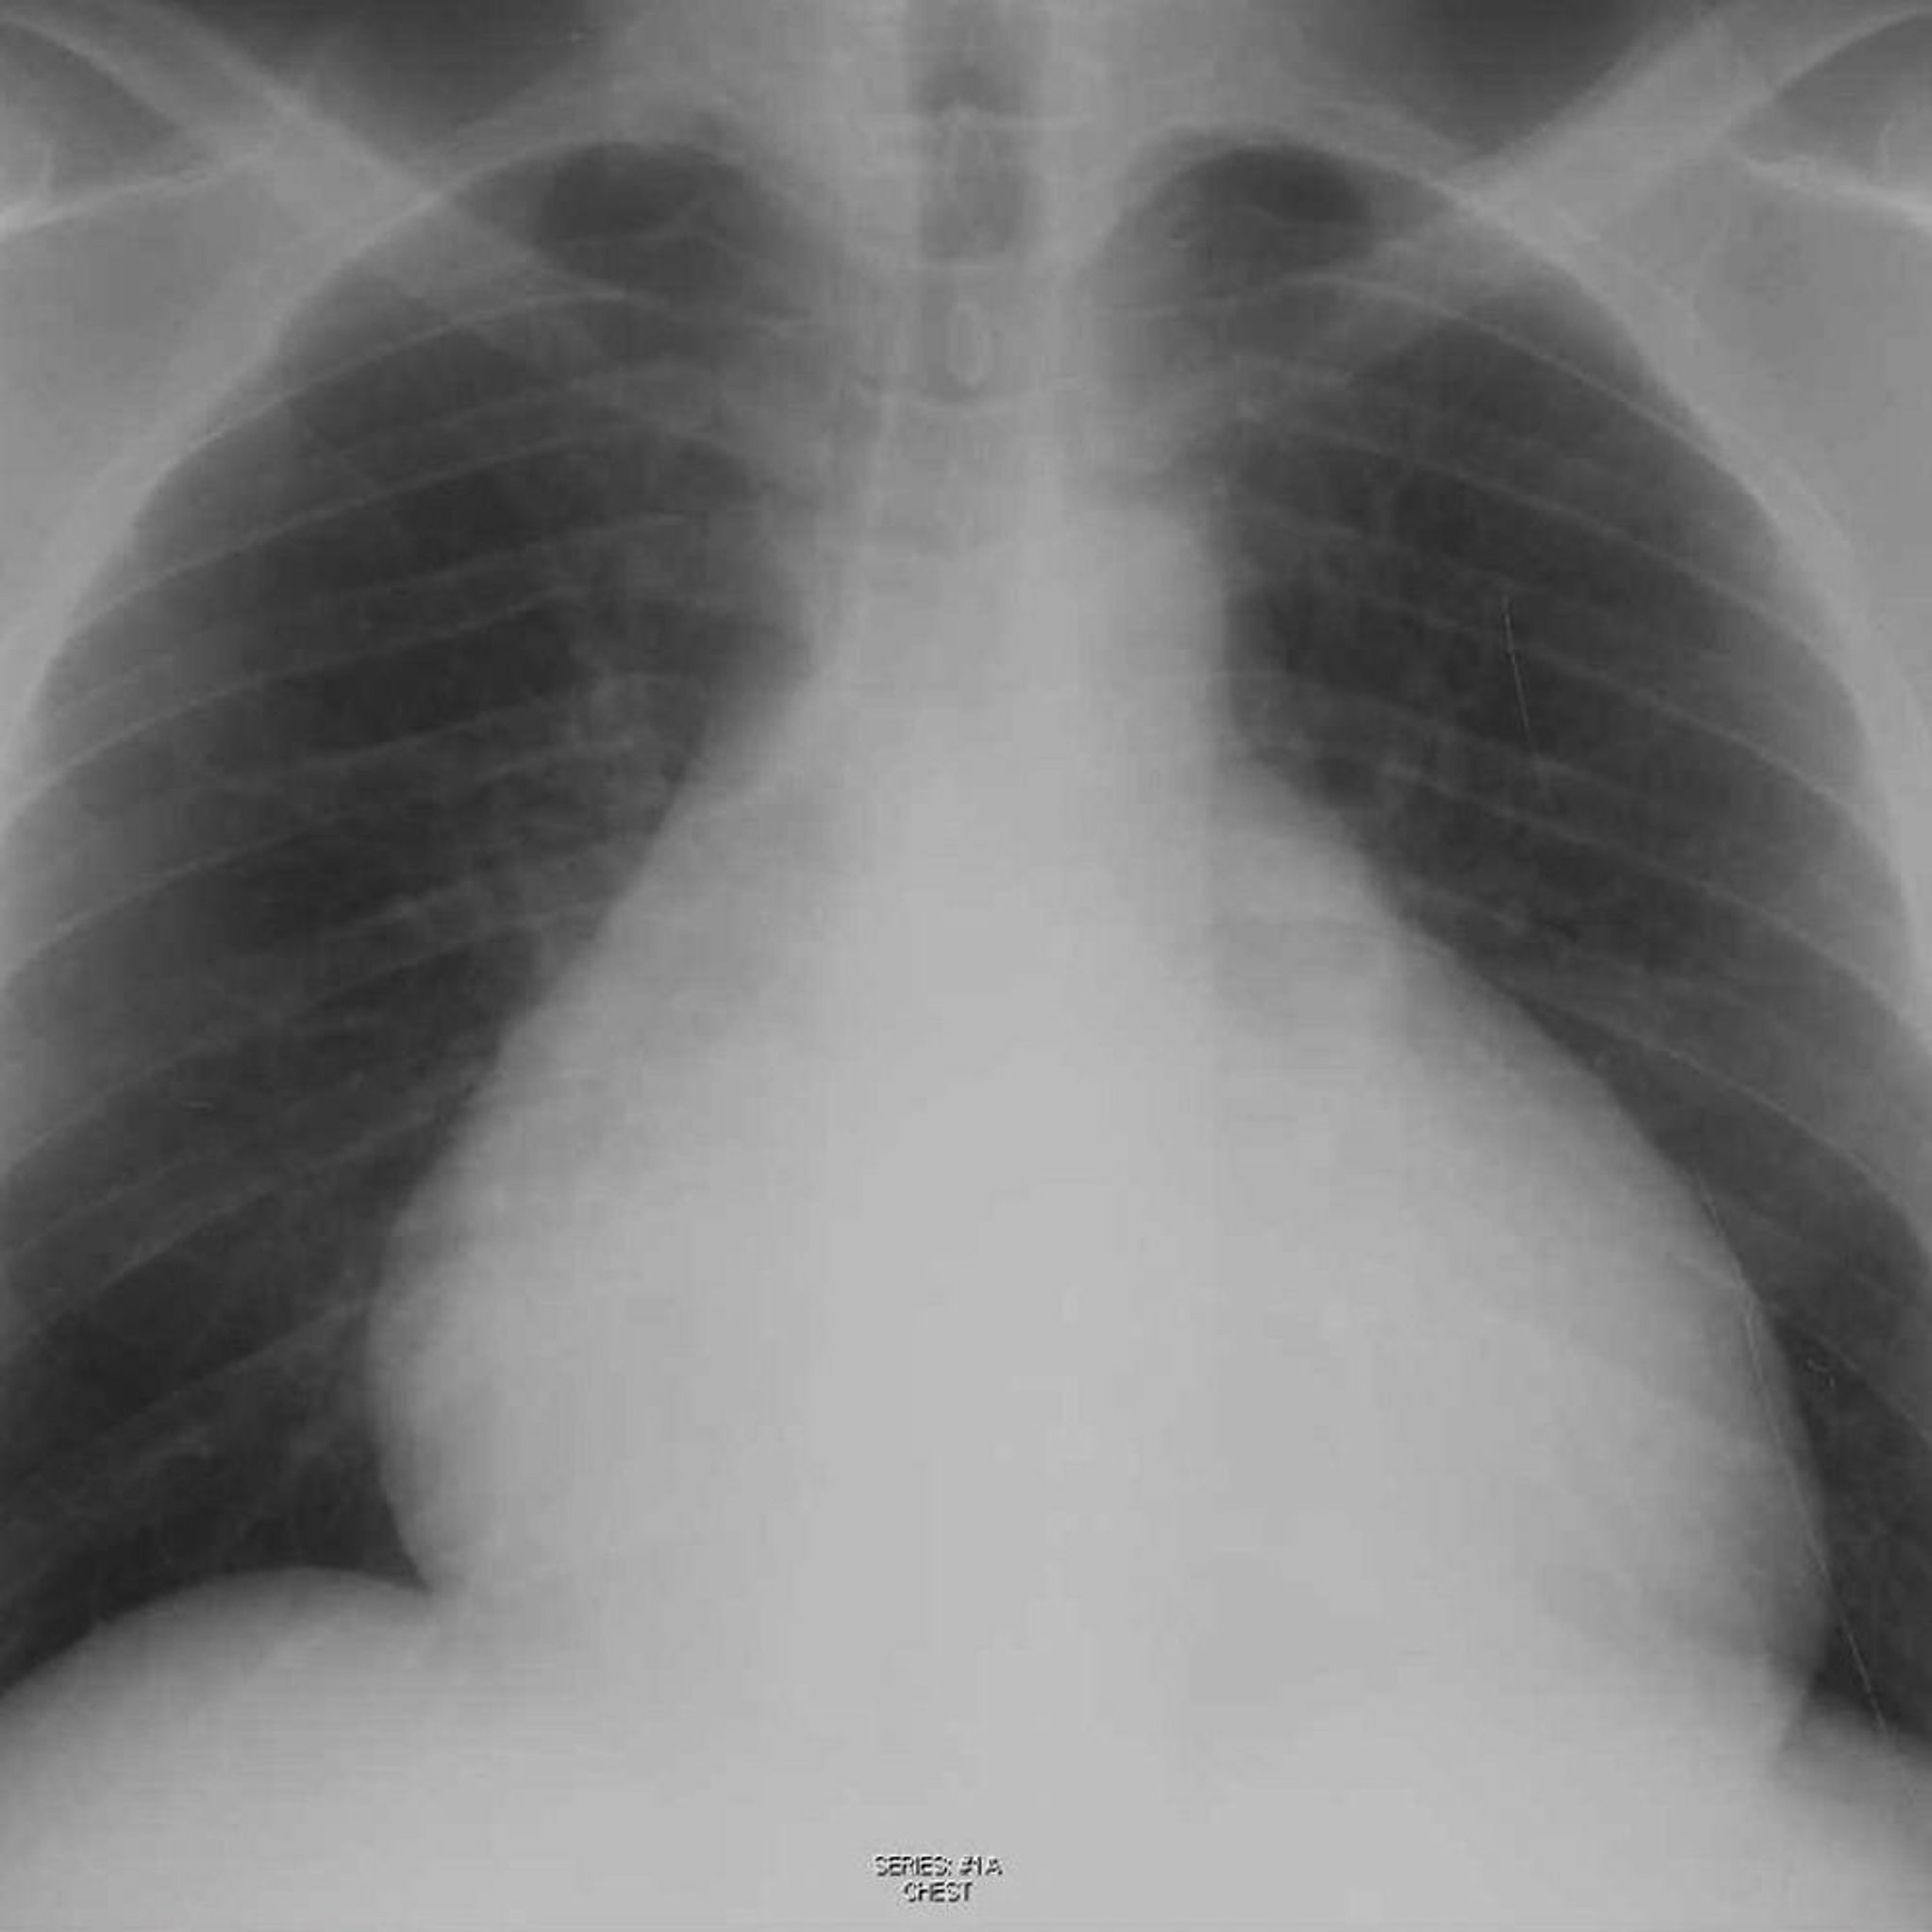

Перикардіальний випіт

Pericardial effusion is often painless, but when it occurs with acute pericarditis, pain may be present. Considerable amounts of pericardial fluid may muffle heart sounds, increase the area of cardiac dullness, and change the size and shape of the cardiac silhouette. A pericardial rub may be heard. With large effusions, compression of the base of the left lung can decrease breath sounds (heard near the left scapula) and cause crackles. Arterial pulse, jugular venous pulse, and blood pressure are normal unless intrapericardial pressure increases substantially, causing tamponade.

Diagnosis is suggested by clinical findings but often is suspected only after finding an enlarged cardiac silhouette on chest radiograph. On ECG, QRS voltage is often decreased, and sinus rhythm remains in most patients. With large, chronic effusions, the ECG may show electrical alternans (ie, P, QRS, or T wave amplitude increases and decreases on alternate beats). Electrical alternans is associated with variation in cardiac position (swinging heart).